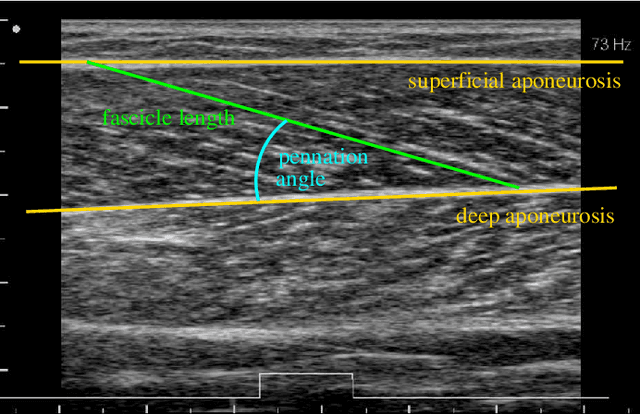

Abstract:We compare four different algorithms for automatically estimating the muscle fascicle angle from ultrasonic images: the vesselness filter, the Radon transform, the projection profile method and the gray level cooccurence matrix (GLCM). The algorithm results are compared to ground truth data generated by three different experts on 425 image frames from two videos recorded during different types of motion. The best agreement with the ground truth data was achieved by a combination of pre-processing with a vesselness filter and measuring the angle with the projection profile method. The robustness of the estimation is increased by applying the algorithms to subregions with high gradients and performing a LOESS fit through these estimates.